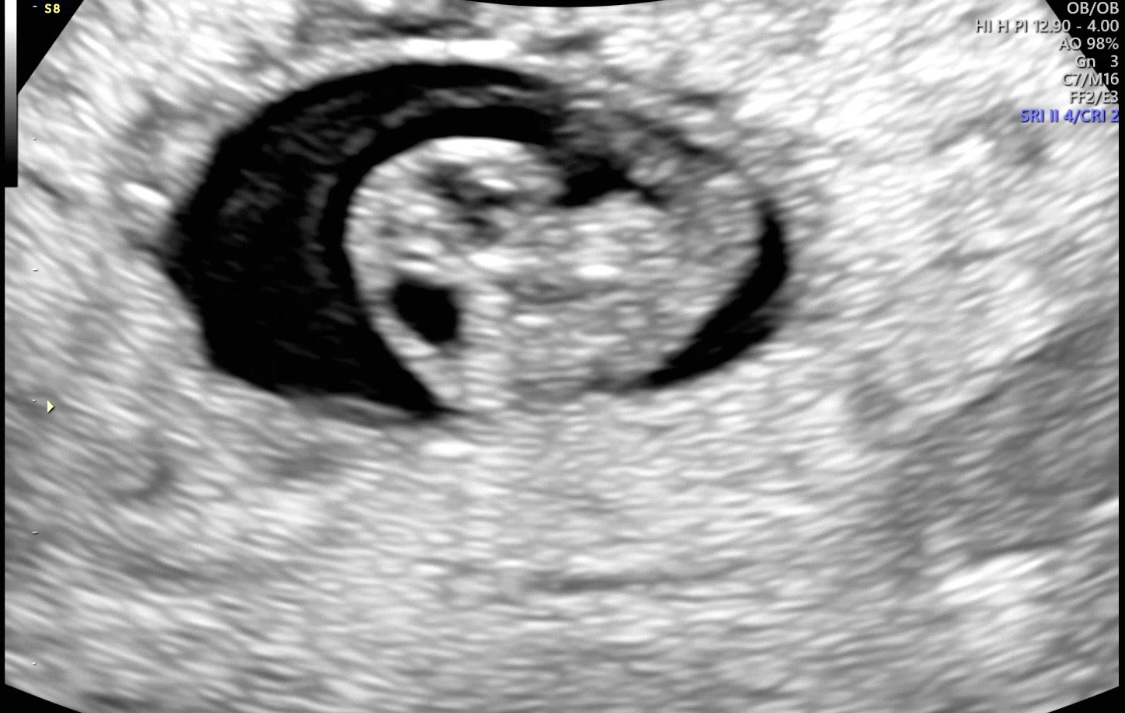

| 가슴 떨리는 임신 이야기를 공유해 주세요. | 6주 5일쯤, 아이의 첫 심장 소리를 들었을 때 마음이 뭉클하면서 울컥했습니다. 지금은 8주 차에 접어들었고, 건강하게 쑥쑥 자라는 아이를 보면 신기하고 고맙고 대견스럽습니다. |

| 치료 도중 느꼈던 가장 기뻤던 순간과 절망적인 것들은 무엇인가요? 잊지 못할 경험이 있나요? | 가장 기뻤던 순간은 초음파를 볼 때마다 아이가 자라고 있는 모습을 확인할 때였습니다. 반대로 절망적이었던 순간은 가끔 피가 비쳐 무섭고 걱정스러웠던 때였는데, 그럴 때마다 이경훈 원장님께서 자주 초음파를 봐주시며 “아이도 괜찮고, 몸 상태도 양호하다”고 말씀해주셔서 큰 위로가 되었습니다. |